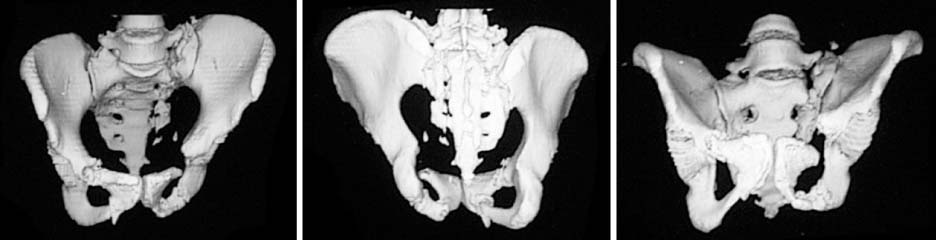

Three-dimensional computed tomography shows superior and posterior migration along with internal rotation and flexion deformity of the left hemipelvis.

Fig. 4 Three-dimensional computed tomography shows superior and posterior migration along with internal rotation and flexion deformity of the left hemipelvis.